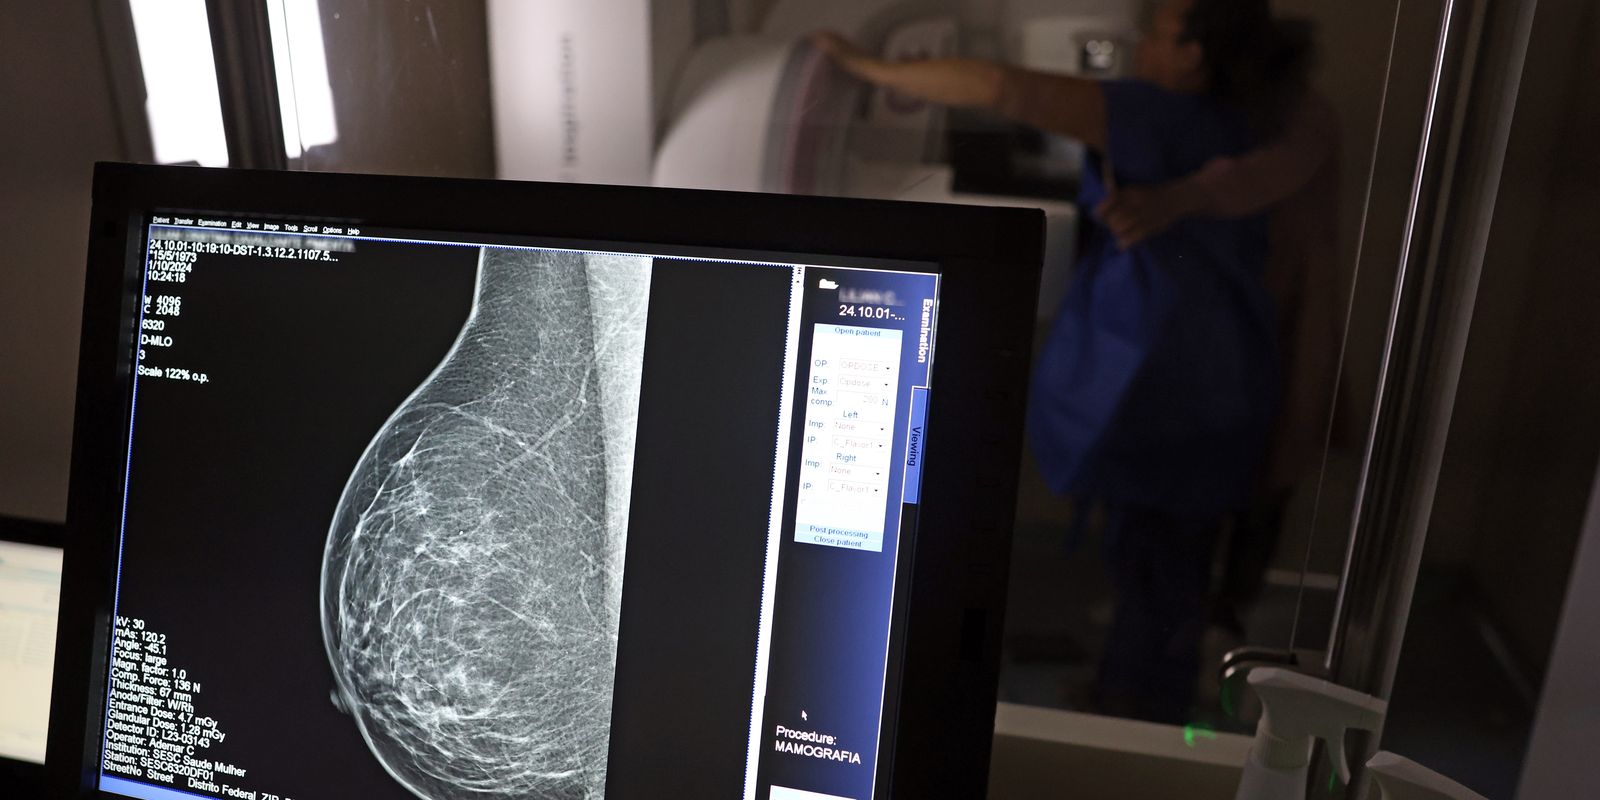

Segundo as pesquisadoras, enquanto o diagnóstico convencional de câncer é feito por meio de exames clínicos, complementados por uma biópsia do tumor para avaliação por um médico patologista, o teste genômico adota uma abordagem mais detalhada e procura biomarcadores moleculares específicos para cada tipo de câncer, como a presença dos genes BRCA1/BRCA2, cruciais para o câncer de mama, ou mutações no gene BRAF, associadas ao câncer de pele. Essas pistas indicam se há alteração e qual a condição de desenvolvimento, mostrando por exemplo se há células em metástase.